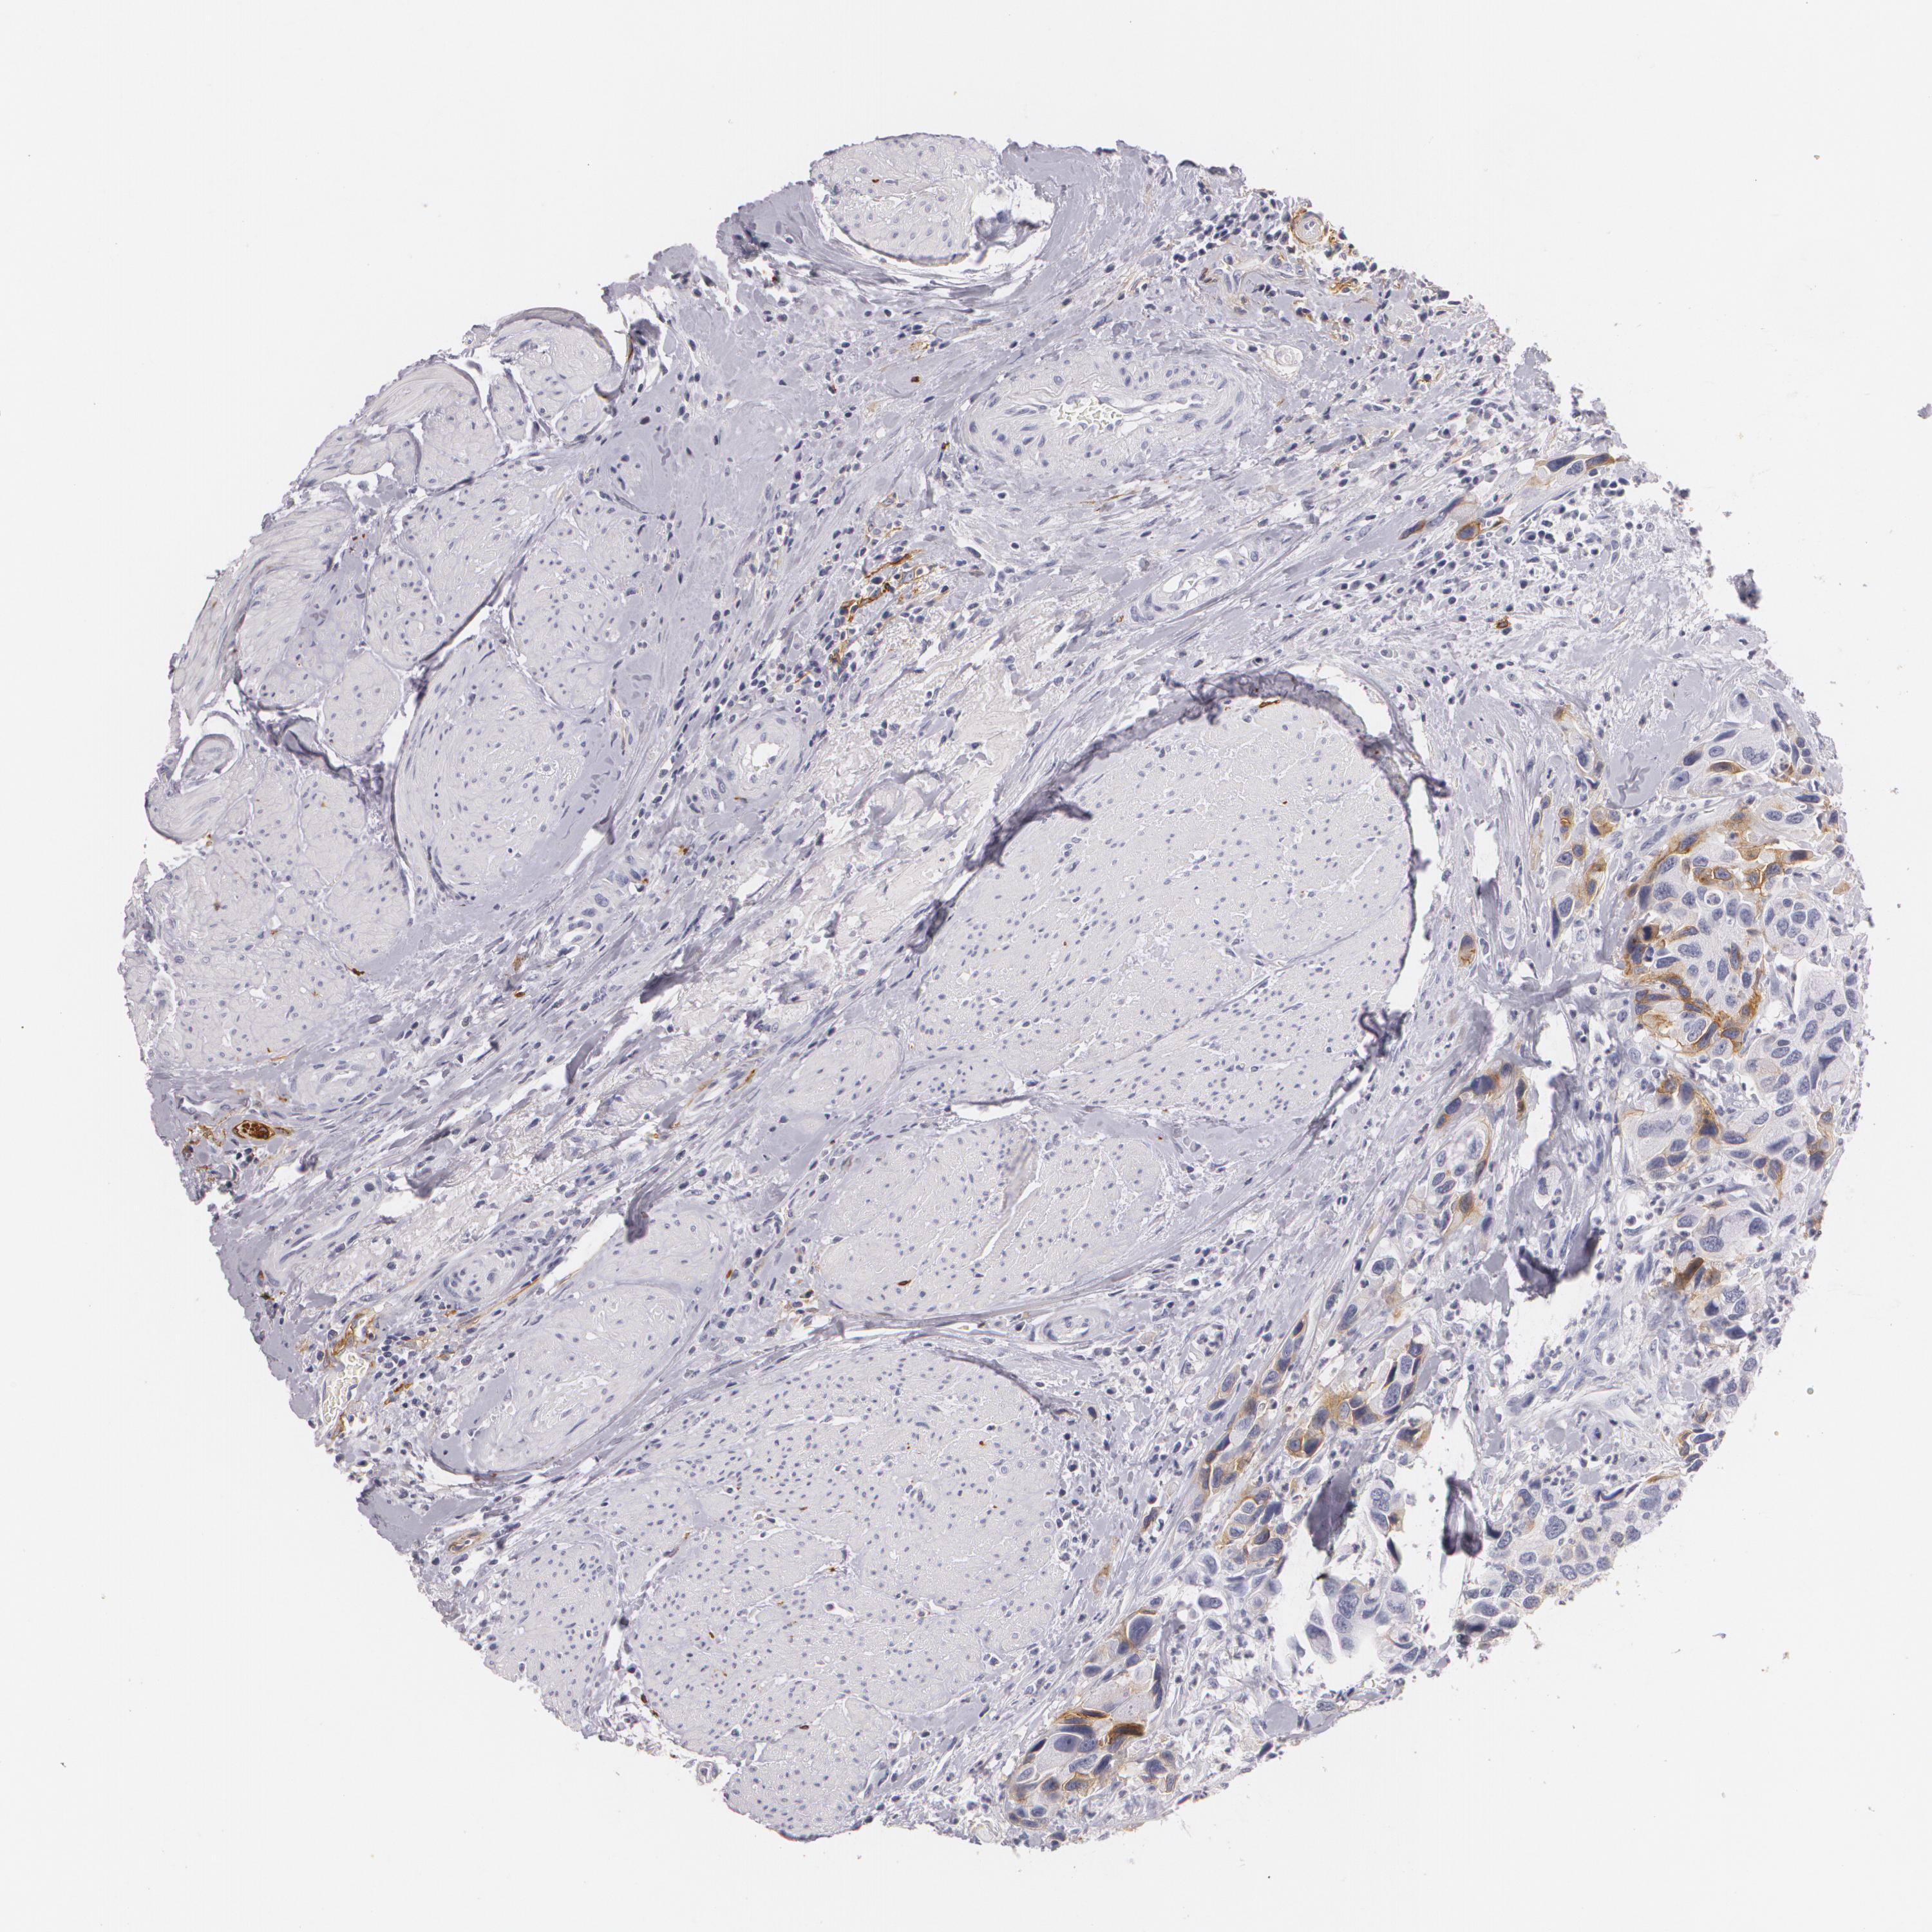

UROTHELIAL CANCER - Protein expressioni

A mouse-over function shows sample information and annotation data. Click on an image to view it in a full screen mode. Samples can be filtered based on level of antibody staining by selecting one or several of the following categories: high, medium, low and not detected. The assay and annotation is described here.

Antibody stainingi

Antibody staining in the annotated cell types in the current human tissue is reported as not detected, low, medium, or high, based on conventional immunohistochemistry profiling in selected tissues. This score is based on the combination of the staining intensity and fraction of stained cells.

Each image is clickable and will lead to virtual microscopy that enables deeper exploration of all samples and also displays staining intensity scores, fraction scores and subcellular localization as well as patient and tissue information for each sample.

Antibody HPA004765

Antibody CAB000143

Antibody CAB001995

Staining

High

Medium

Low

Not detected

Intensity

Strong

Moderate

Weak

Negative

Quantity

>75%

75%-25%

<25%

None

Location

Nuclear

Cytoplasmic/membranous

Cytoplasmic/membranous,nuclear

Urothelial carcinoma, High grade

Urothelial carcinoma, Low grade

Adenocarcinoma, NOS